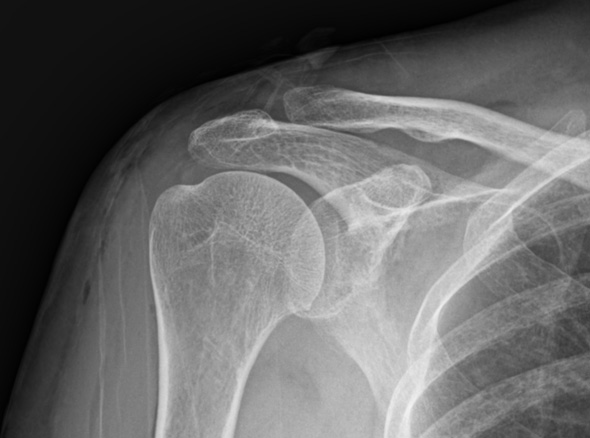

어깨 힘줄 내부에 칼슘 석회가 침착되어 힘줄의 손상과 함께 통증을 유발하는 질환입니다.

석회화건염은 외상으로 인해서 발생하는 것과 무관합니다.

주로 40대 연령층에서 흔하게 발생하는 질환입니다.

석회화건염은 어깨 질환중 갑작스럽게 통증이 나타나는 경우가 많이 있습니다.

어깨 속에 석회가루가 쌓여 통증을 유발하는 석회화건염은

석회는 신체 어느 부위에서나 발생할 수 있으나 어깨에 가장 많이 발생합니다.